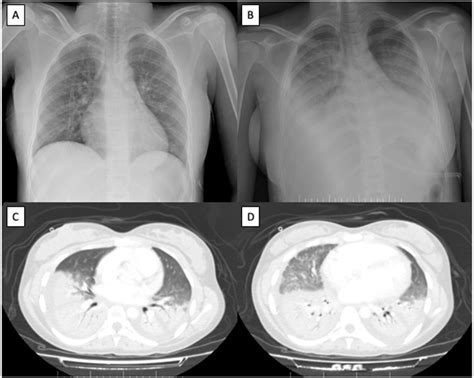

Acute Chest Syndrome is defined by the presence of a new pulmonary infiltrate on a chest X-ray, combined with clinical symptoms such as fever, cough, chest pain, sputum production, dyspnea, or hypoxia. While often triggered by a vaso-occlusive crisis or infection, the pathophysiology is multifactorial. In SCD, sickled red blood cells are rigid and misshapen, causing them to adhere to the endothelium and block blood flow, which leads to inflammation and injury within the lung tissue. This creates a feedback loop of worsening oxygen deficiency and further sickling, which necessitates immediate medical attention.

Once a patient is admitted, medical teams use a combination of diagnostics to confirm the diagnosis and assess severity. Standard procedures typically include pulse oximetry, chest radiography, and arterial blood gas analysis. Treatment is comprehensive and aggressive, focusing on reversing the sickling process and supporting respiratory function.